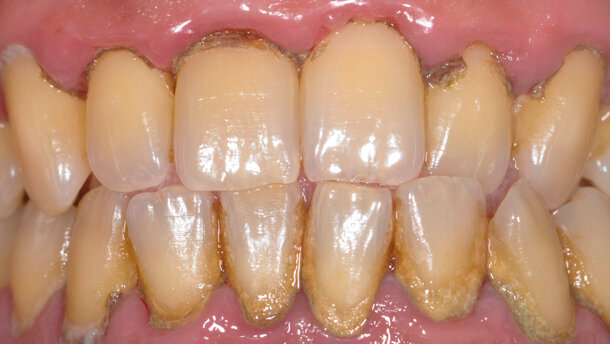

Si ripresenta alla nostra attenzione a marzo 2014 (dopo 6 anni) paziente di 39 anni, sempre fumatore, spiegandoci che ha avuto dei problemi e non è più potuto tornare ai normali richiami di igiene. All’esame obiettivo, si osserva infiammazione diffusa dei tessuti gengivali, manifestata da sanguinamento evidente ed edema generalizzato (Fig. 4), si osserva una numerosa quantità di placca e tartaro sopra e sotto gengiva con danno a livello parodontale in tutti i quattro quadranti (Fig. 5). Si nota una malocclusione tra il sestante 2 e il sestante 5.

Il paziente ci riferisce che ha smesso di usare tutti gli ausili precedentemente consigliati e usa solo lo spazzolino manuale quando capita e, paragonata alla prima visita del 2009, la carica batterica è aumentata e il suo livello di igiene è peggiorato.